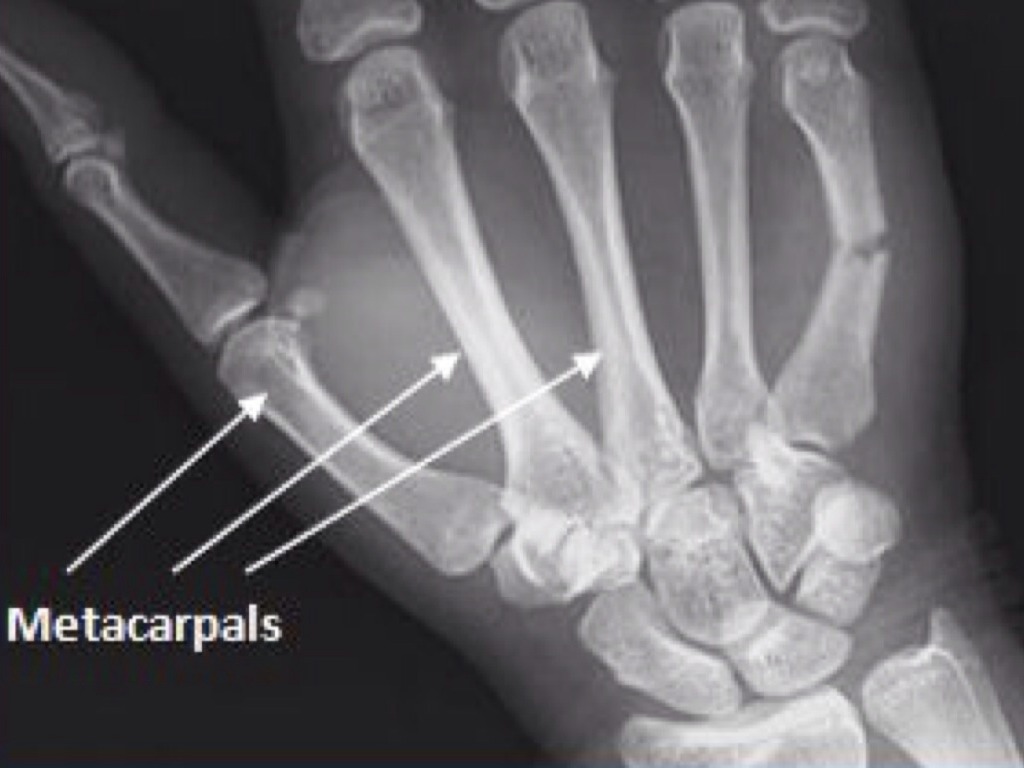

The batter suffers a boxers fracture of the fifth metatarsal